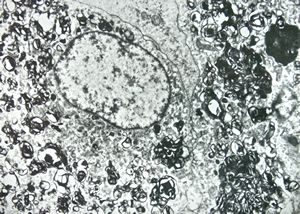

M,43y. | blood - degraded Candida (bone marrow suppression)

M,18y. | blood - clin. susp. leukemia - degraded Candida